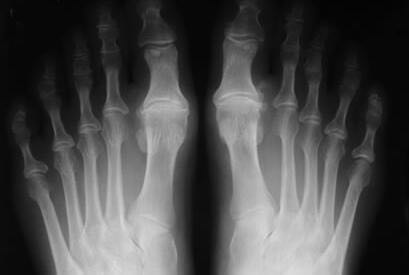

Hallux Rigidus: Qué es y cómo se trata

El “hallux rigidus” es una patología que produce una disminución de movimiento de la primera articulación metatarsofalángica del dedo gordo del pie…